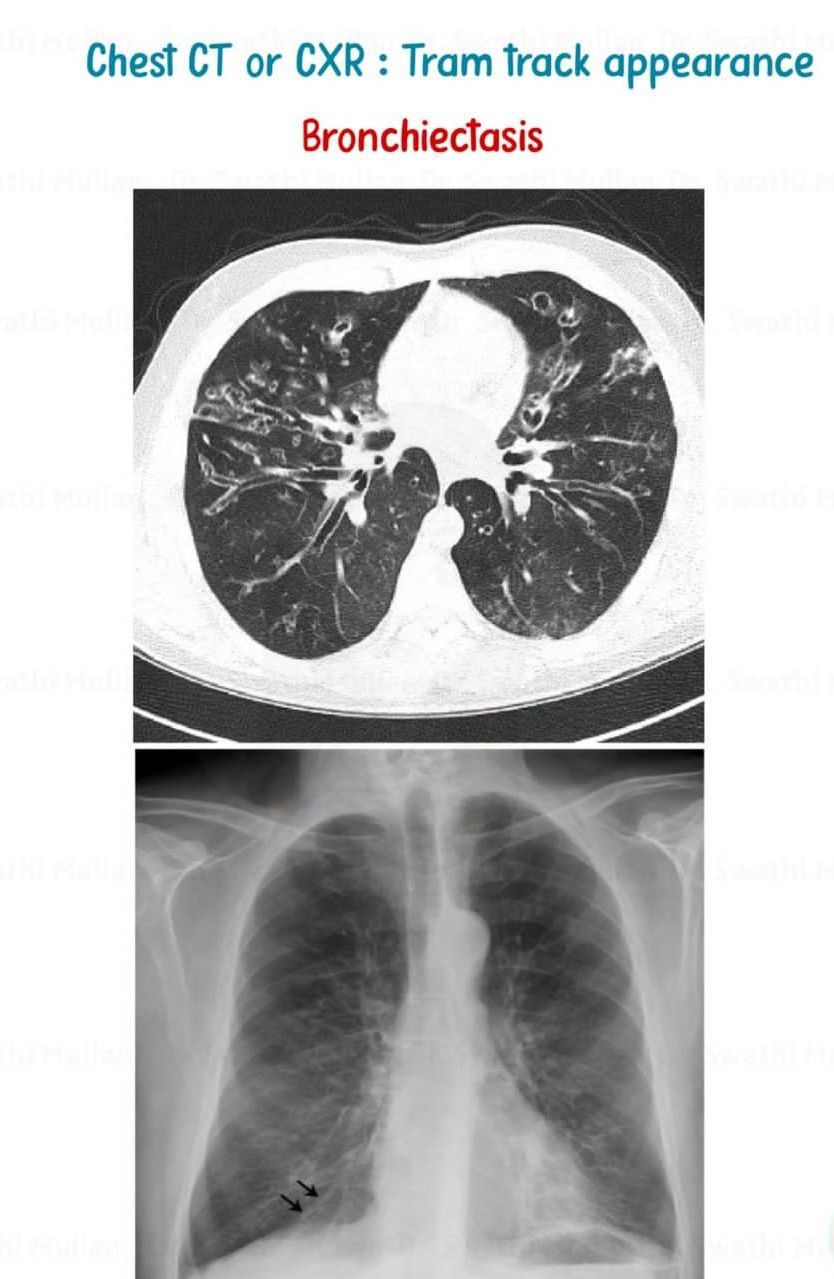

Tram Track Appearance IV

Tram track appearances or tram track signs are medical signs that bear some resemblance to tramway tracks. They are seen in different conditions By: https://www.instagram.com/p/C6ifvK7B6ia/?utm_source=ig_web_copy_link